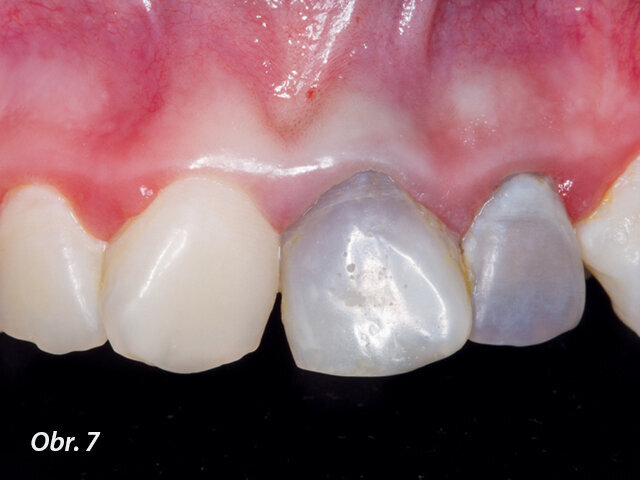

U pacienta v 10 letech byla pro úrazovou ztrátu vitality provedena revaskularizace na zubu 22. Po 2týdenní aplikaci kombinace antibiotik do prostoru pouze chemicky dekontaminovaného kořene byl po vyvolání krvácení aplikován prostředek PRGF a kořen uzavřen pomocí MTA. Zub byl rekonstruován kompozitem. Na kontrole po 5 letech je viditelně zvětšený objem tkáně kořene a absence projasnění. (Obr. 4–6)

Častou komplikací (téměř inherentní součástí) tohoto ošetření je zbarvení korunek ošetřených zubů, které je následně po vytvoření kořenové tkáně nutno řešit vnitřním bělením (obr. 7).